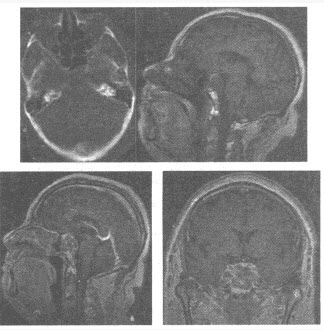

A:CT检查的价值在于有助于分期、治疗计划的制订及疗效观察

B:Ⅰ期限于腔内肿块,无胃壁增厚,无邻近或远处转移

C:Ⅱ期胃壁厚度>1cm但未超出胃壁

D:凡有胃周淋巴结肿大的均属于晚期胃癌

E:Ⅲ期胃壁增厚,侵犯邻近器官,但无远处转移

F:Ⅳ期有远处转移的征象